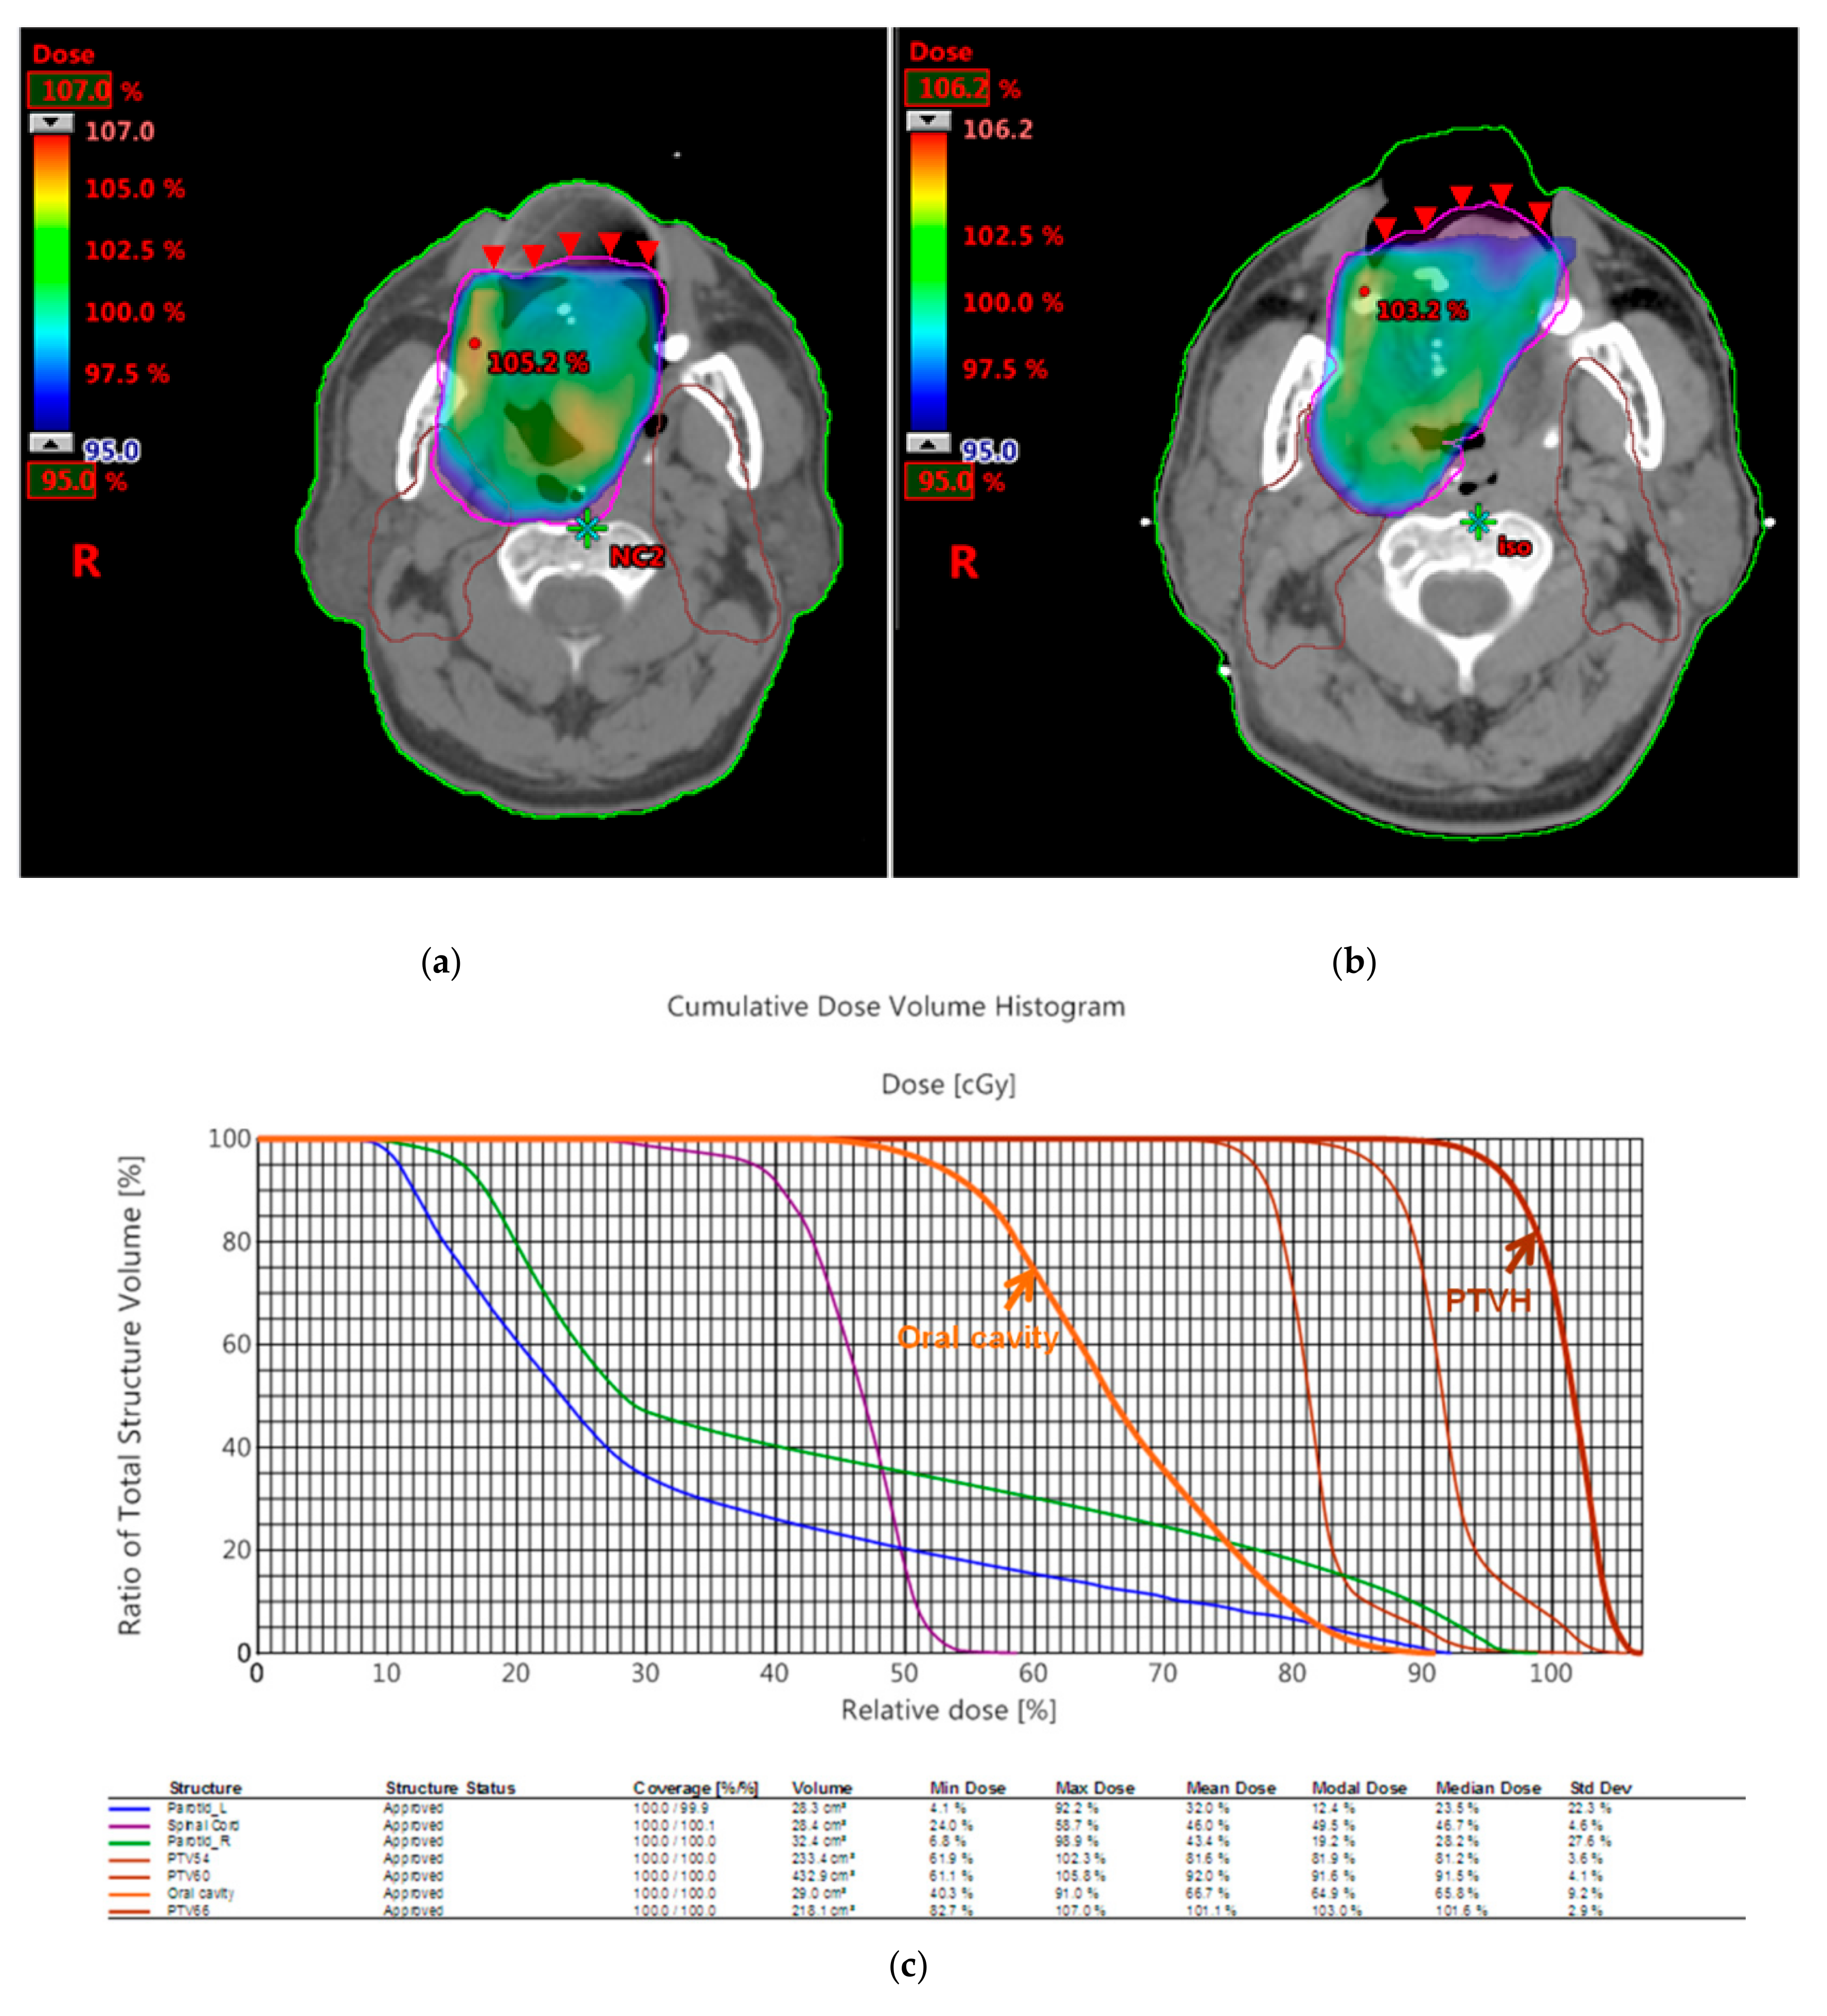

3.2. Dosimetric Comparison

| Patient 2 | 3D Printed Bite Blocks | Conventional Oral Corks |

|---|---|---|

| PTV D100% | 98% | 97% |

| PTVmax | 103% | 106.1% |

| PTVmin | 90.3% | 89.3% |

| CI | 0.99 | 1.00 |

| HI | 1.08 | 1.12 |

| V26 of right parotid gland | 38% | 70% |

| V26 of left parotid gland | 34% | 68% |